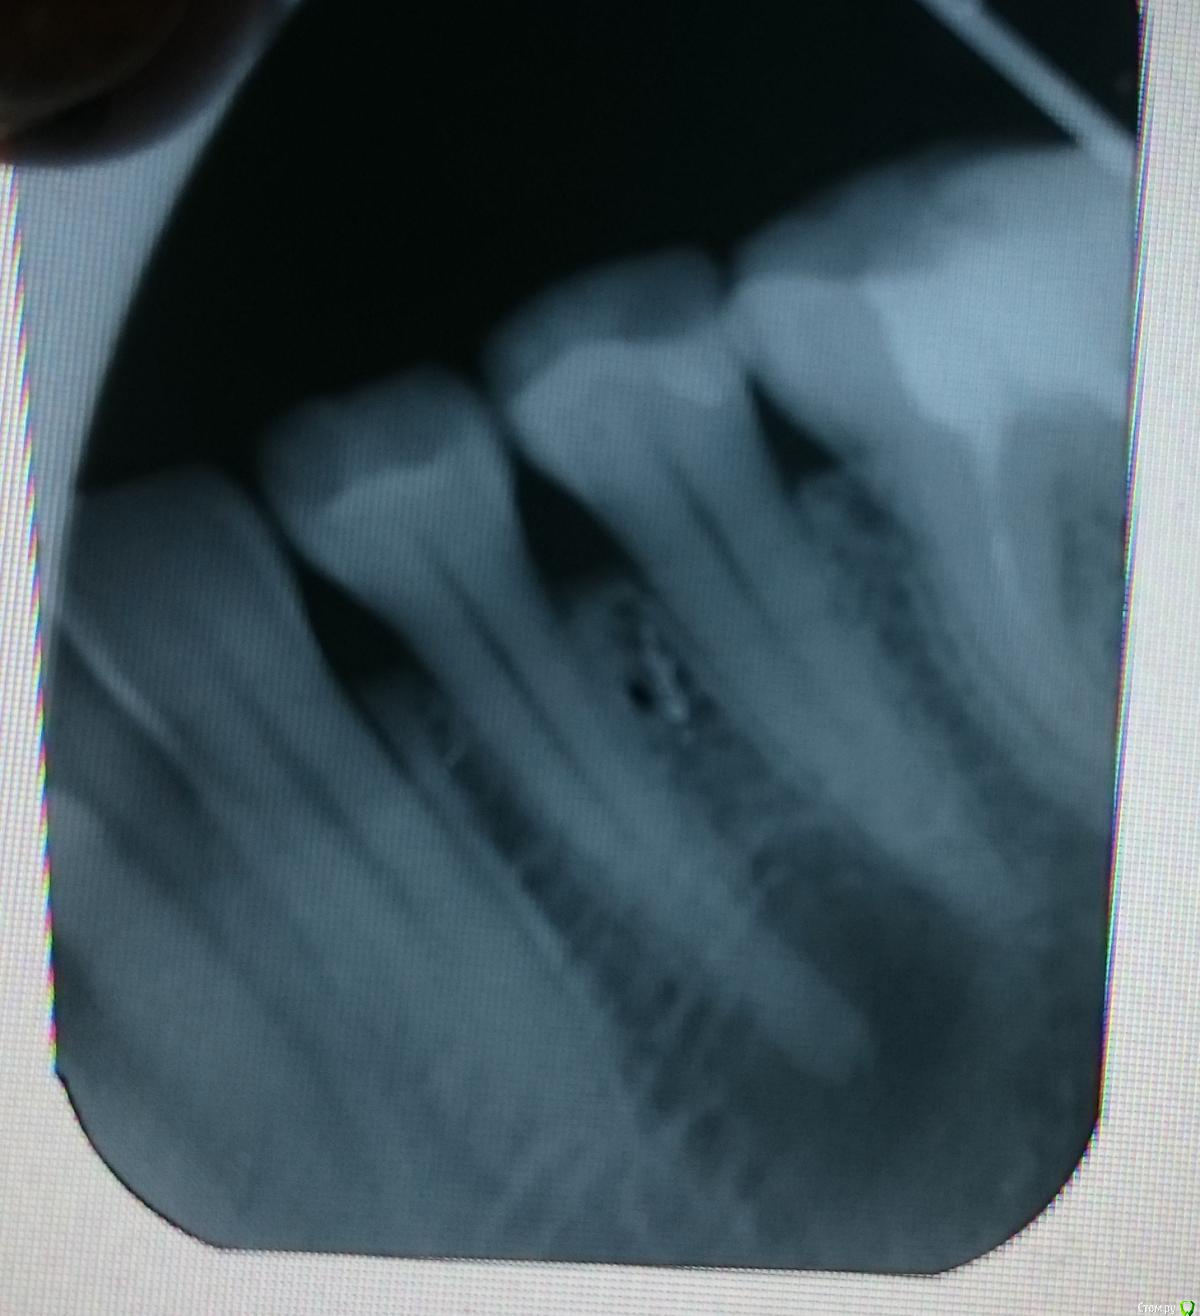

good customer Опубликовано 12 июля, 2016 Автор Поделиться Опубликовано 12 июля, 2016 (изменено) Добрый вечер!Была на консультации. Врач сказал, что на витальность проверять не надо, т.к. будет депульпация......сделала прицельный снимок. Изменено 12 июля, 2016 пользователем good customer Ссылка на комментарий

good customer Опубликовано 28 июля, 2016 Автор Поделиться Опубликовано 28 июля, 2016 добрый вечер, уважаемые Врачи. предложили план лечения 44. Ссылка на комментарий

DmitrySH Опубликовано 5 августа, 2016 Поделиться Опубликовано 5 августа, 2016 Зуб ранее не лечен, у него очень хорошие шансы на благоприятный исход.Стекловолокно сильно лишнее(еще и 2 раза). Коронковая часть зуба сохранена.Потребуется микродоступ, около 1*1.5 (2) мм. Зуб останется практически целым. Ссылка на комментарий